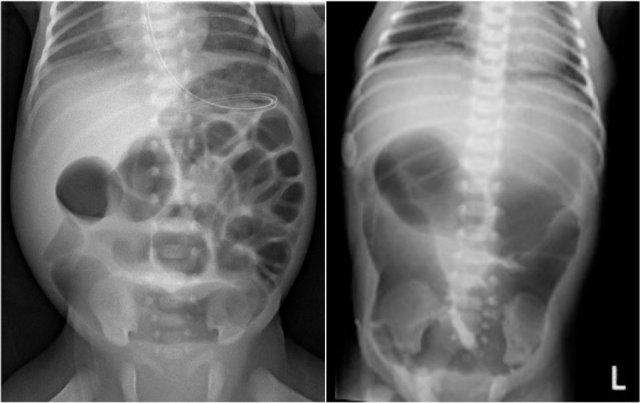

Đây là hình ảnh của một trẻ sơ sinh phát triển viêm ruột hoại tử.

Ở giai đoạn sớm này, X-quang chỉ cho thấy hình ảnh giãn ruột không đặc hiệu.

Ở giai đoạn này, không thể xác lập chẩn đoán.

Hình ảnh bên trái được chụp 6 ngày sau sinh, cho thấy ruột giãn với khí trong thành ruột.

Hình chụp thụt tháo đại tràng lúc 6 tuần tuổi cho thấy hẹp ở đại tràng xuống (mũi tên).